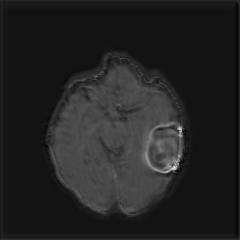

We argue that the sub-optimal paradigm of processing different abstractions within a single CNN pipeline can be remedied through the effective processing of information in a structured manner. Consequently, we devise strategies for disentangling the edge and texture information within a single training pipeline. Figure 2 illustrates how our proposed module, dubbed EG-CNN, can be paired with any existing CNN encoder-decoder to improve segmentation quality near intensity edges. We have applied our EG-CNN to the tasks of brain and liver tumor segmentation in medical images (Figure 3).

(1) Brain MR (2) Liver MR (3) Liver CT (4) Lung CT